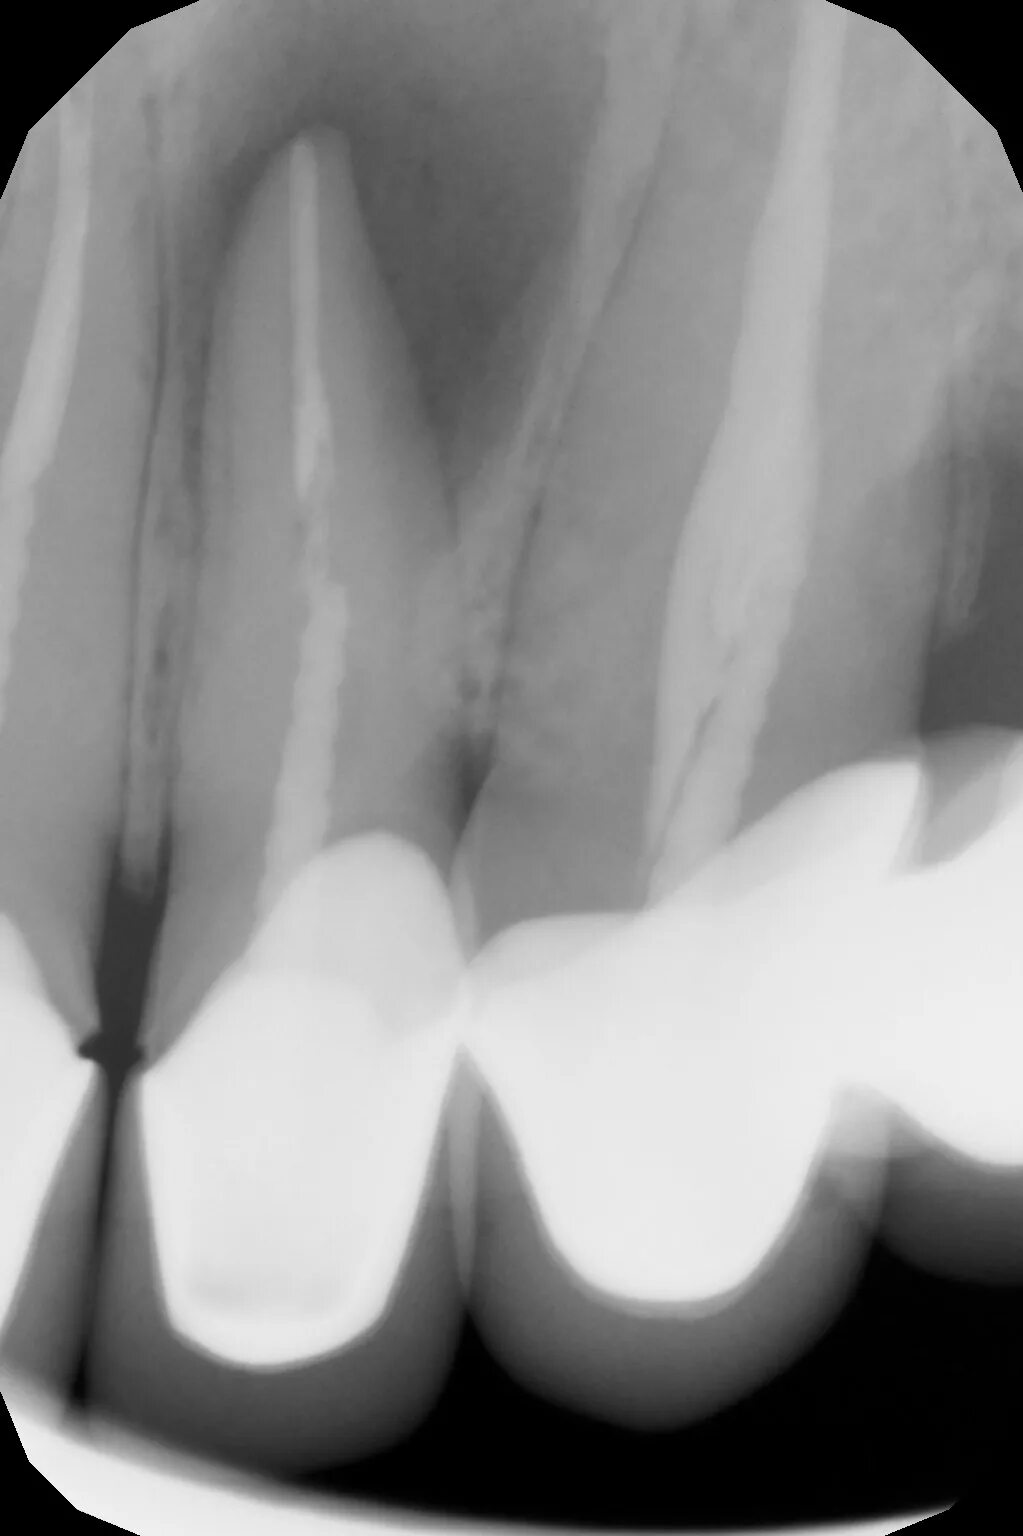

Киста зуба что это